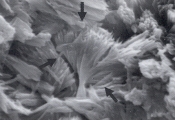

Рис. 3. Сканированная электронная микрофотография некоторых маленьких кристаллов, описанных в рис.2 (увеличение Х 1,800).

Кальция карбонат может кристаллизоваться в моче лошадей, кроликов, коз, образуя большие желто-коричневые или бесцветные сфероиды с радиальной исчерченностью, или маленькие кристаллы круглой, овальной или гантелеобразной формы (рис. 2 и 3). У собак и кошек эти кристаллы обычно не обнаруживаются. Если в моче обнаруживается гантелеобразный кристалл, то это скорее кальция оксалат моногидрат.

Рис. 2. Микрофотография кристаллов кальция карбоната в мочевом осадке 7-летней кобылы (не окрашено, увеличение Х160